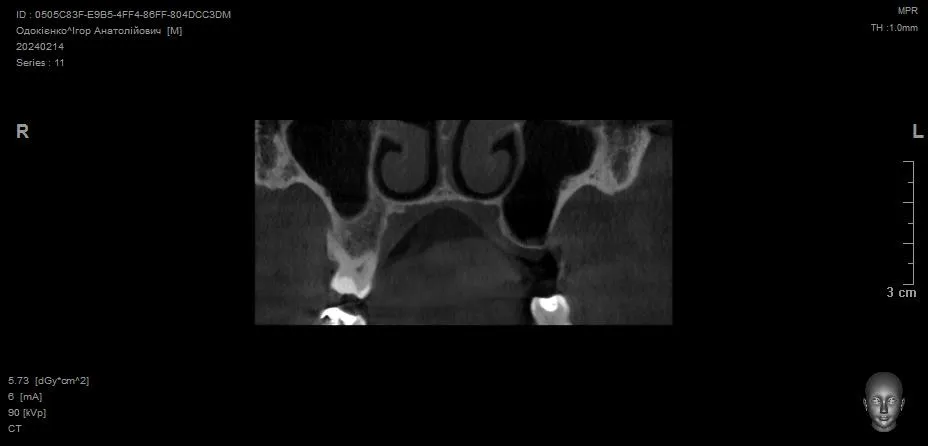

Відкритий синус-ліфтинг